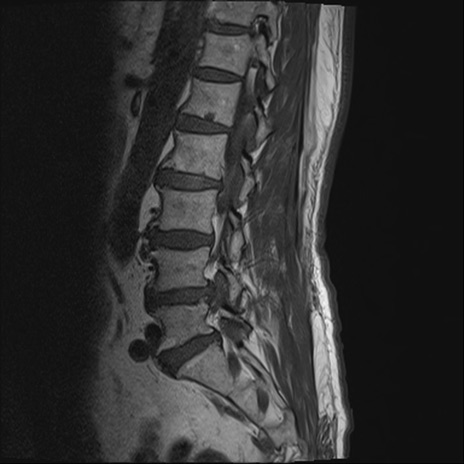

【整形】TIPS症例2 腰椎MRI T1WI(矢状断像)

【症例】70歳代男性

【主訴】左下肢痛

【現病歴】2週間前くらいから腰痛、左下肢痛あり。左臀部から大腿、下腿外側のしびれが常時ある。歩行とともに同部位の痛みあり。

【身体所見】Lasegue70-/60+、Bragard-/±、PTR ±/±、ATR -/-、IP 5/5、TA 5/4、TS 5/5、EHL 右第1足趾なし/3、FHL 5/5、hypersthesia(-)、足背動脈触知良好

異常所見と診断は?